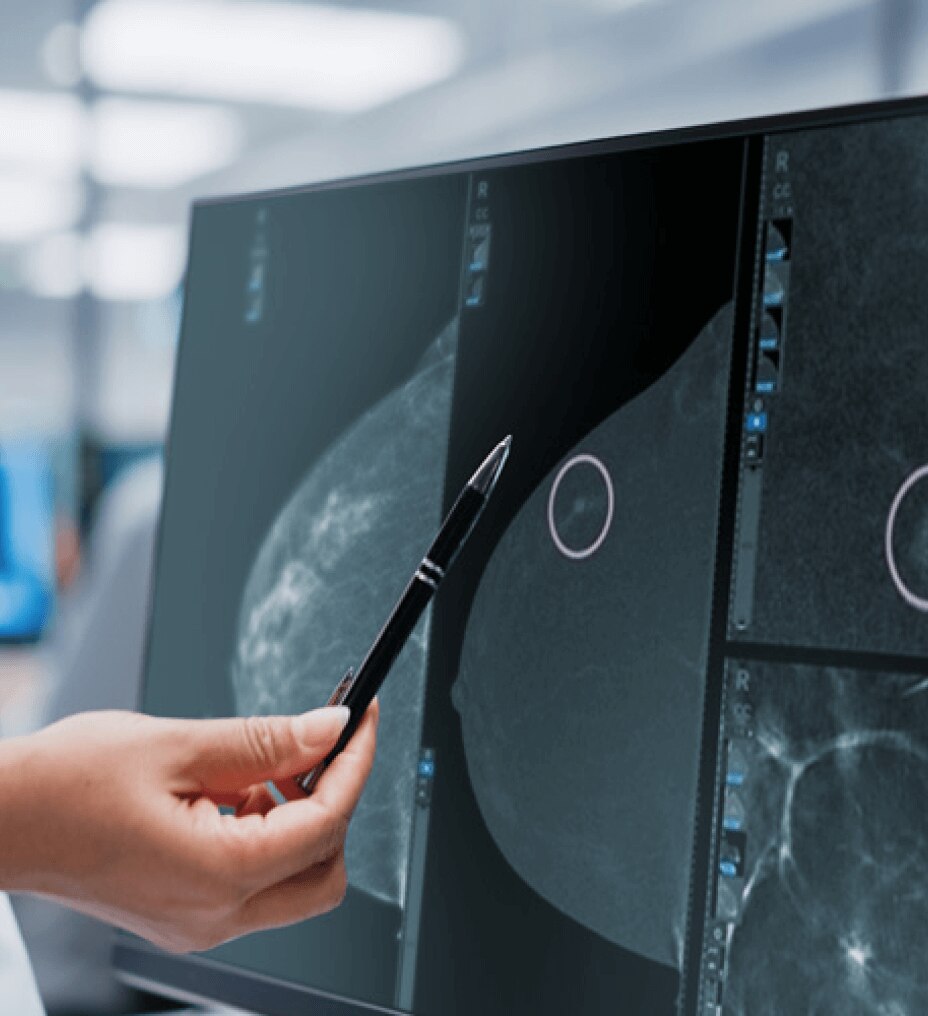

マンモグラフィ